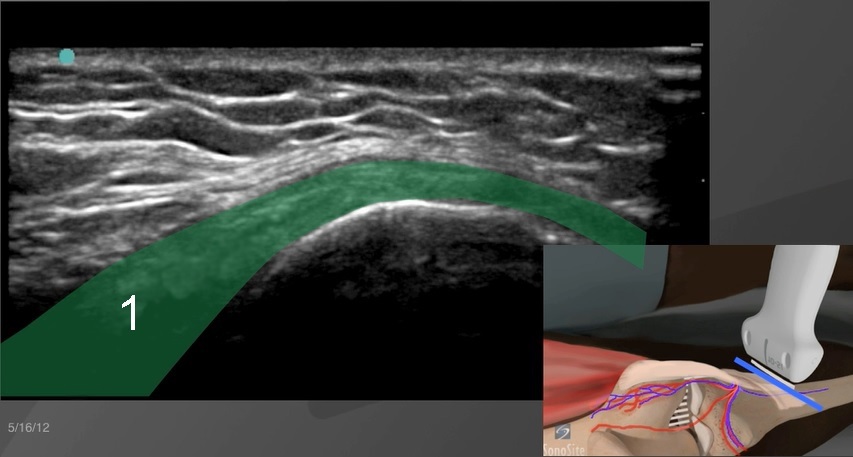

膝足アンセリンmp複合画像

足アンセリンの複合